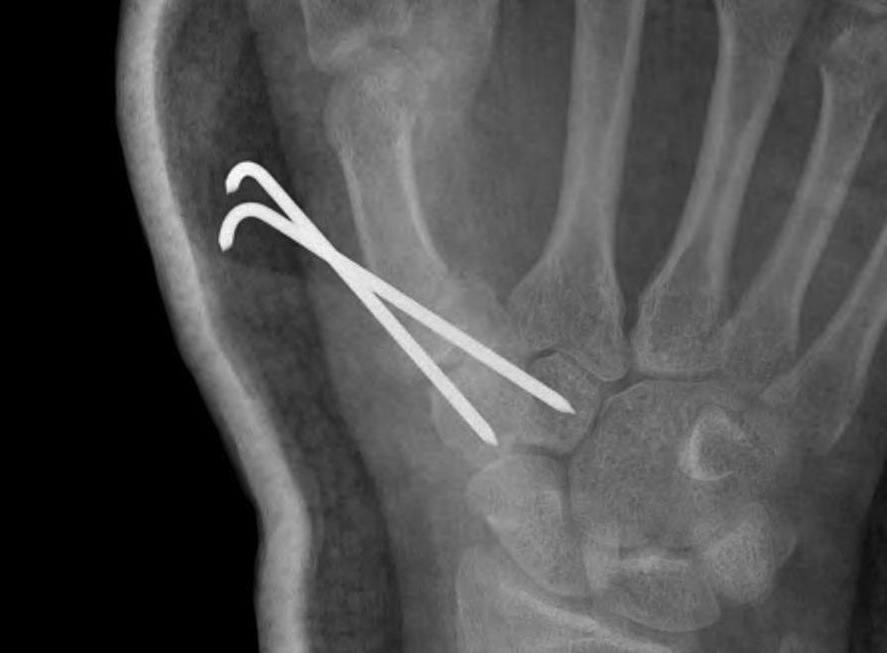

A. Bennett's Fracture

Fracture

- oblique intra-articular fracture

- small volar fragment remains in situ as attached to beak ligament

- metacarpal displaces proximally and dorsally due to APL

- inherently unstable

Management

Closed reduction

- longitudinal traction on metacarpal

- use thumb to reduce metacarpal shaft

- use 2 x K wires to pin metacarpal to trapezium / trapezoid

- 6 weeks in thumb spica cast